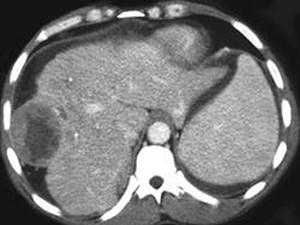

问题 女,47岁,曾患乙肝,现右上腹及肝区疼痛、腹胀,消瘦乏力半月,AFP阳性,CT扫描如图,请选择最可能答案 ( )

选项 A、肝转移瘤 B、肝包虫病 C、肝血管瘤 D、肝脓肿 E、肝癌

答案 E